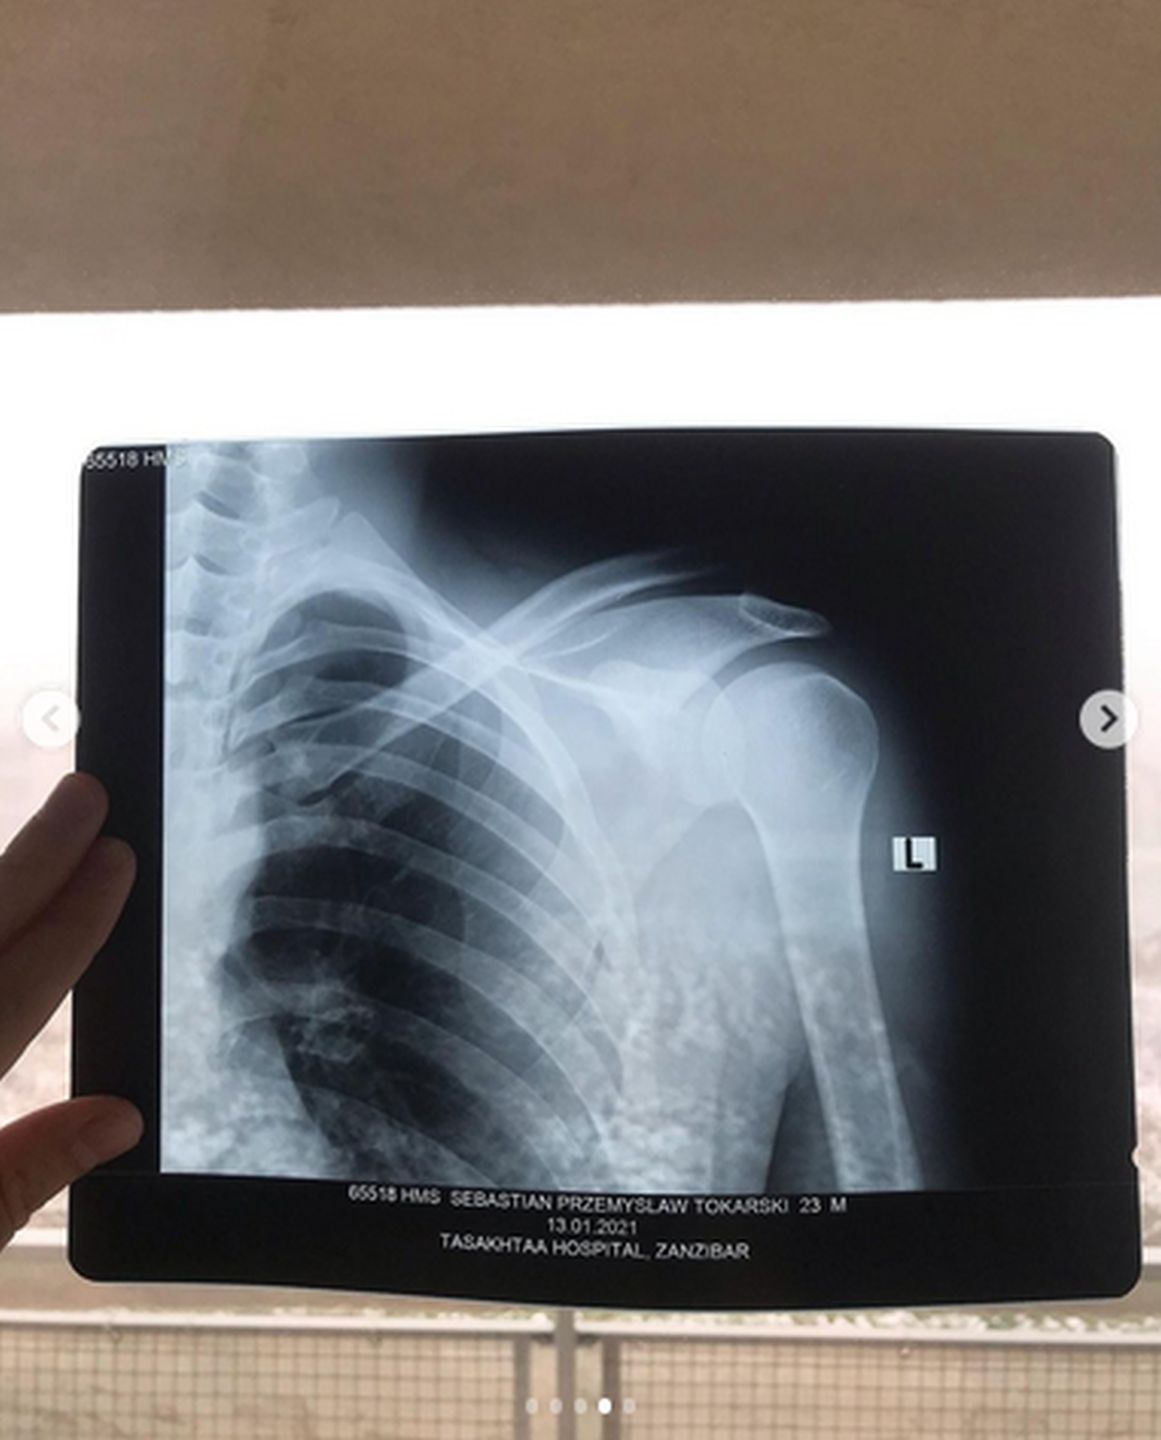

Jakiś czas temu jedna z beztroskich "zabaw" poszukujących miłości w kurorcie na Zanzibarze uczestników 3. edycji Hotelu Paradise zakończyła się dramatycznie. Podnoszony przez kolegę Sebastian niefortunnie upadł na posadzkę, nie tylko tracąc przytomność, ale i poważnie uszkadzając bark. W efekcie Tokarski zmuszony był zakończyć przygodę z show TVN7 i wrócić do Polski, gdzie przeszedł operację. W związku z tym, że zabieg nie przyniósł oczekiwanych rezultatów, koledzy z programu postanowili uruchomić zbiórkę na jego dalsze leczenie.